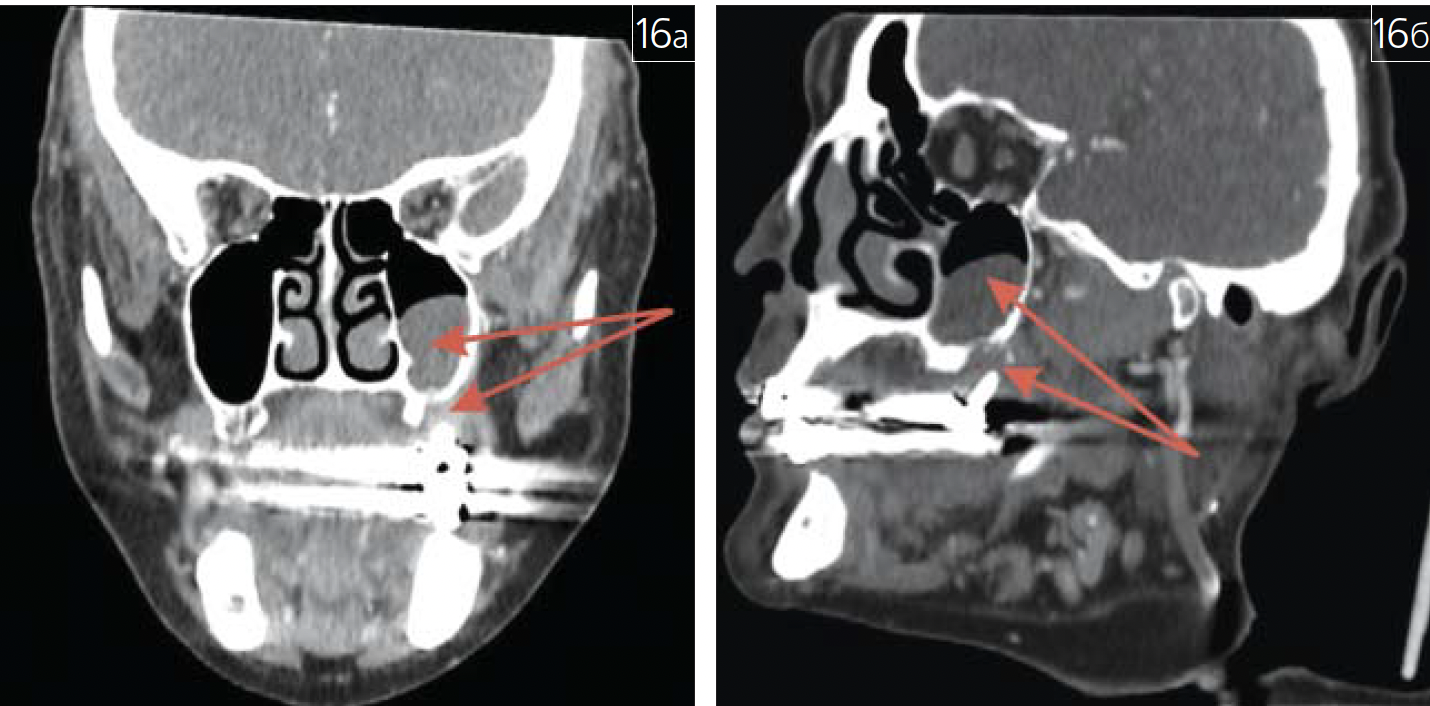

Патологическое новообразование может выступать симптомом первичной или вторичной опухоли костной ткани (рис. 2; 3 а-в),

Рис. 3. Остеогенная саркома черепа на МСКТ черепа (показана красными стрелками): а – трехмерная реконструкция; б – аксиальная проекция; в – плоскостная реконструкцияв корональной плоскости